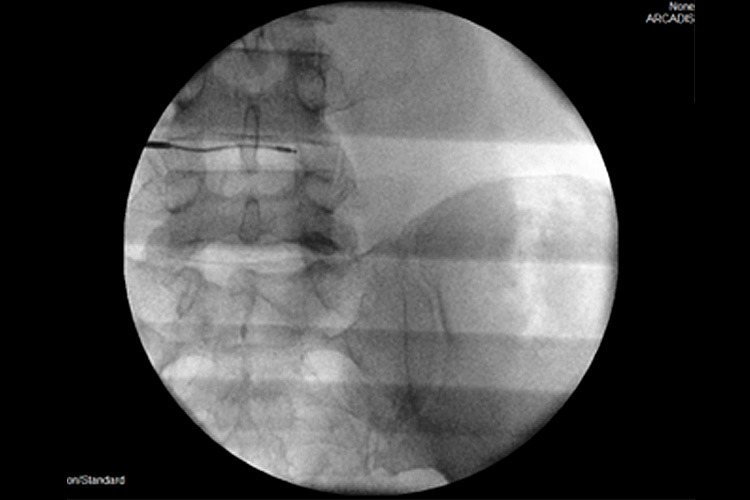

Χρησιμοποιώντας την εφαρμογή ραδιοσυχνοτήτων, εισάγεται, αρχικά, ένας οδηγός κάτω από ακτινοσκοπικό έλεγχο στον μεσοσπονδύλιο δίσκο και κατευθύνεται έμπροσθεν της κήλης. Μέσα από τον οδηγό εισάγεται ένα ηλεκτρόδιο, που η άκρη του έχει τη δυνατότητα κίνησης και στροφής 360ᵒ (Σχ. 1).

Το ηλεκτρόδιο υπερθερμαίνεται μέσα από μια πηγή σε θερμοκρασία 40ᵒC - 70ᵒC (coblation – low temperature ablation). Είναι μια μέθοδος, που χρησιμοποιεί ηλεκτρόδιο ραδιοσυχνοτήτων σε χαμηλές θερμοκρασίες για σύντομο χρονικό διάστημα 2’- 3’, χωρίς να καταστρέφει τους παρακείμενους ιστούς, αλλά δρα μόνον στο επιθυμητό σημείο του μεσοσπονδύλιου δίσκου (Σχ 2).

Σχ. 2 Η εισαγωγή του ηλεκτροδίου (RF), δημιουργεί ένα κενό, που βοηθάει στην «ανάταξη» της προβολής του δίσκου.

Περίπτωση 1: Ακτινοσκόπηση σε Διαδερμική Δισκοπλαστική με χρήση ηλεκτροδίου (RF) σε κήλη μεσοσπονδυλίου δίσκου Ο4-Ο5. |